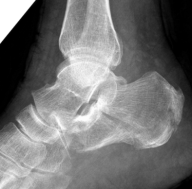

伤后患者的临床表现主要包括:足跟部肿痛、皮下瘀斑、局部压叩痛、足弓变低平、足跟增宽、足底变长以及伤足不能下地负重等。

回到前文所述的患者程某,其X线片及CT检查提示其骨折系波及关节面的严重粉碎性骨折,具有明确的手术指征。

在骨科中心主任吴超的带领下,团队采用了天玑Ⅱ骨科手术机器人为程某开展了微创手术治疗,该手术时间短、创伤小、出血少、透视次数少,同时实现了骨折块的解剖复位和精准的螺钉置入及固定;术后影像学显示患者关节面完全复位,螺钉位置良好,固定可靠。